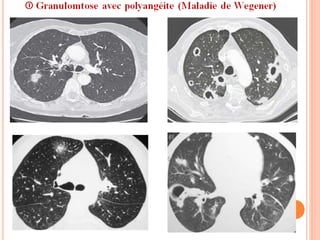

Imagerie thoracique (F+P, TDM):

 Les nodules pulmonaires :

 A limites nettes, de nombres variables, parfois un véritable «

lâcher de ballons » pseudo-tumorale.

 De 5mm à >10 cm, évoluent par ↑ en taille et en nombre, et

par une excavation progressive (50% surtout si >2 cm).

 A paroi épaisse (#abcès, cancer excavé), parfois fine d’allure

bulleuse. Pas de niveau liquide en dehors des surinfections.

 Parfois entourés par un halo en VD une Hgie périnodulaire.

contexte compatible

Multiples Nodules

excavés

GPA